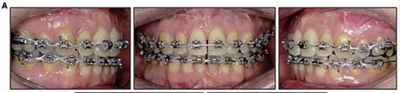

治療結果:

患者側貌改善,下唇唇肌緊張消失,上下唇可自然閉合。磨牙及尖牙關系糾正至I類,覆合覆蓋正常。上下頜弓型糾正至卵圓形,牙弓寬度增加。頭影測量分析示SNA角81.8°,ANB角3°。頭影測量重疊圖示下頜骨向后旋轉,垂直面高度略有增加。

19個月后復查,情況穩(wěn)定,牙弓寬度穩(wěn)定。